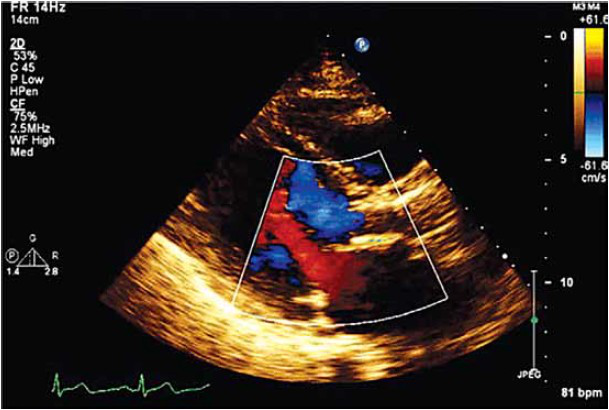

Paciente, 67 anos, sexo feminino, com história de dispneia aos moderados esforços, edema de membros inferiores e palpitações de início há 6 meses. Ao exame físico cardiológico: ritmo cardíaco regular, sopro diastólico aspirativo decrescente com B2 hipofonética, Sopro mesossistólico de hiperfluxo ruflar.

Realizou os exames complementares a seguir:

Diante das evidências clínicas apresentadas, o tratamento preconizado para essa paciente é: